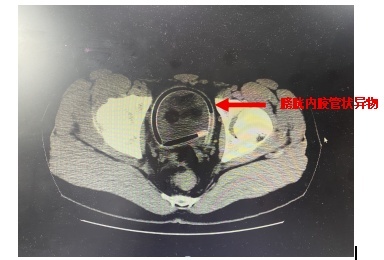

拍片一看

一根橡胶管不偏不倚地

躺在小许的膀胱里

像条蜷缩的小蛇

小许术前CT图像

时间不等人,予完善盆腔及下腹部CT确认有异物存留后,小许转由泌尿外科黄坚副主任医师团队收治,于昨日在膀胱镜下成功取出橡胶管,手术用时仅15分钟。小许恢复良好,已于今日顺利出院。